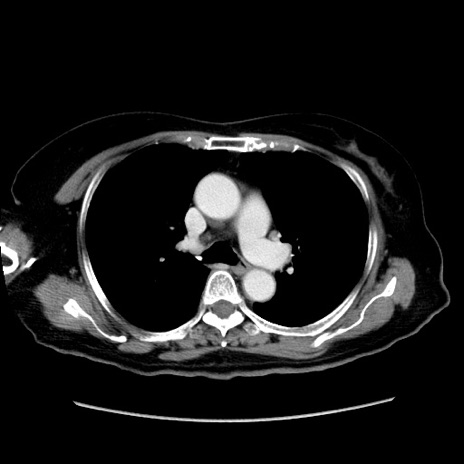

症例19(横断像)

【症例】80歳代女性

【主訴】下腹部痛

【現病歴】約8時間前より下腹部痛の出現あり、救急外来受診。

【既往歴】両側付属器切除

【身体所見】意識清明、下腹部正中に手術痕あり、その部位に一致して圧痛と反跳痛あり。腸蠕動音は亢進。

【データ】WBC 9300、CRP 0.15